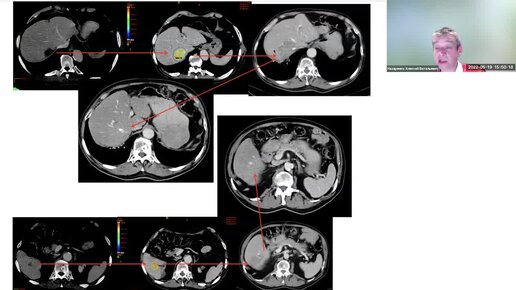

Достижения лучевой терапии- сегодня и завтра